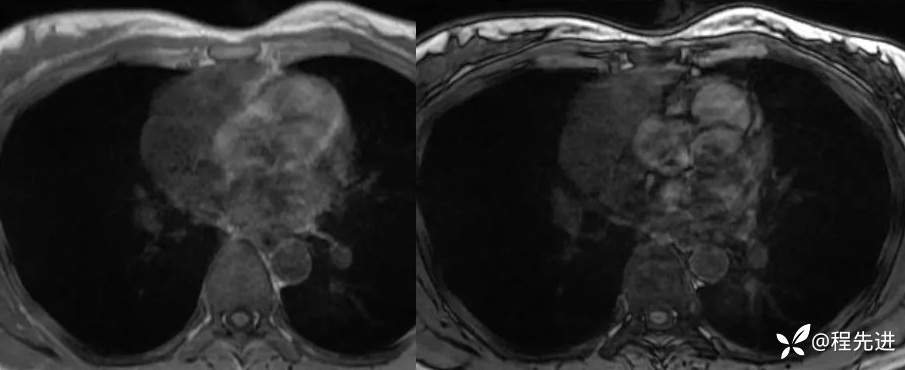

MR

T2抑脂

DWI

同反相位